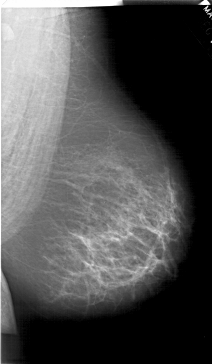

A_1518_1.RIGHT_CC

RIGHT_CC LINES 6871 PIXELS_PER_LINE 4066 BITS_PER_PIXEL 12 RESOLUTION 43.5 NON_OVERLAY